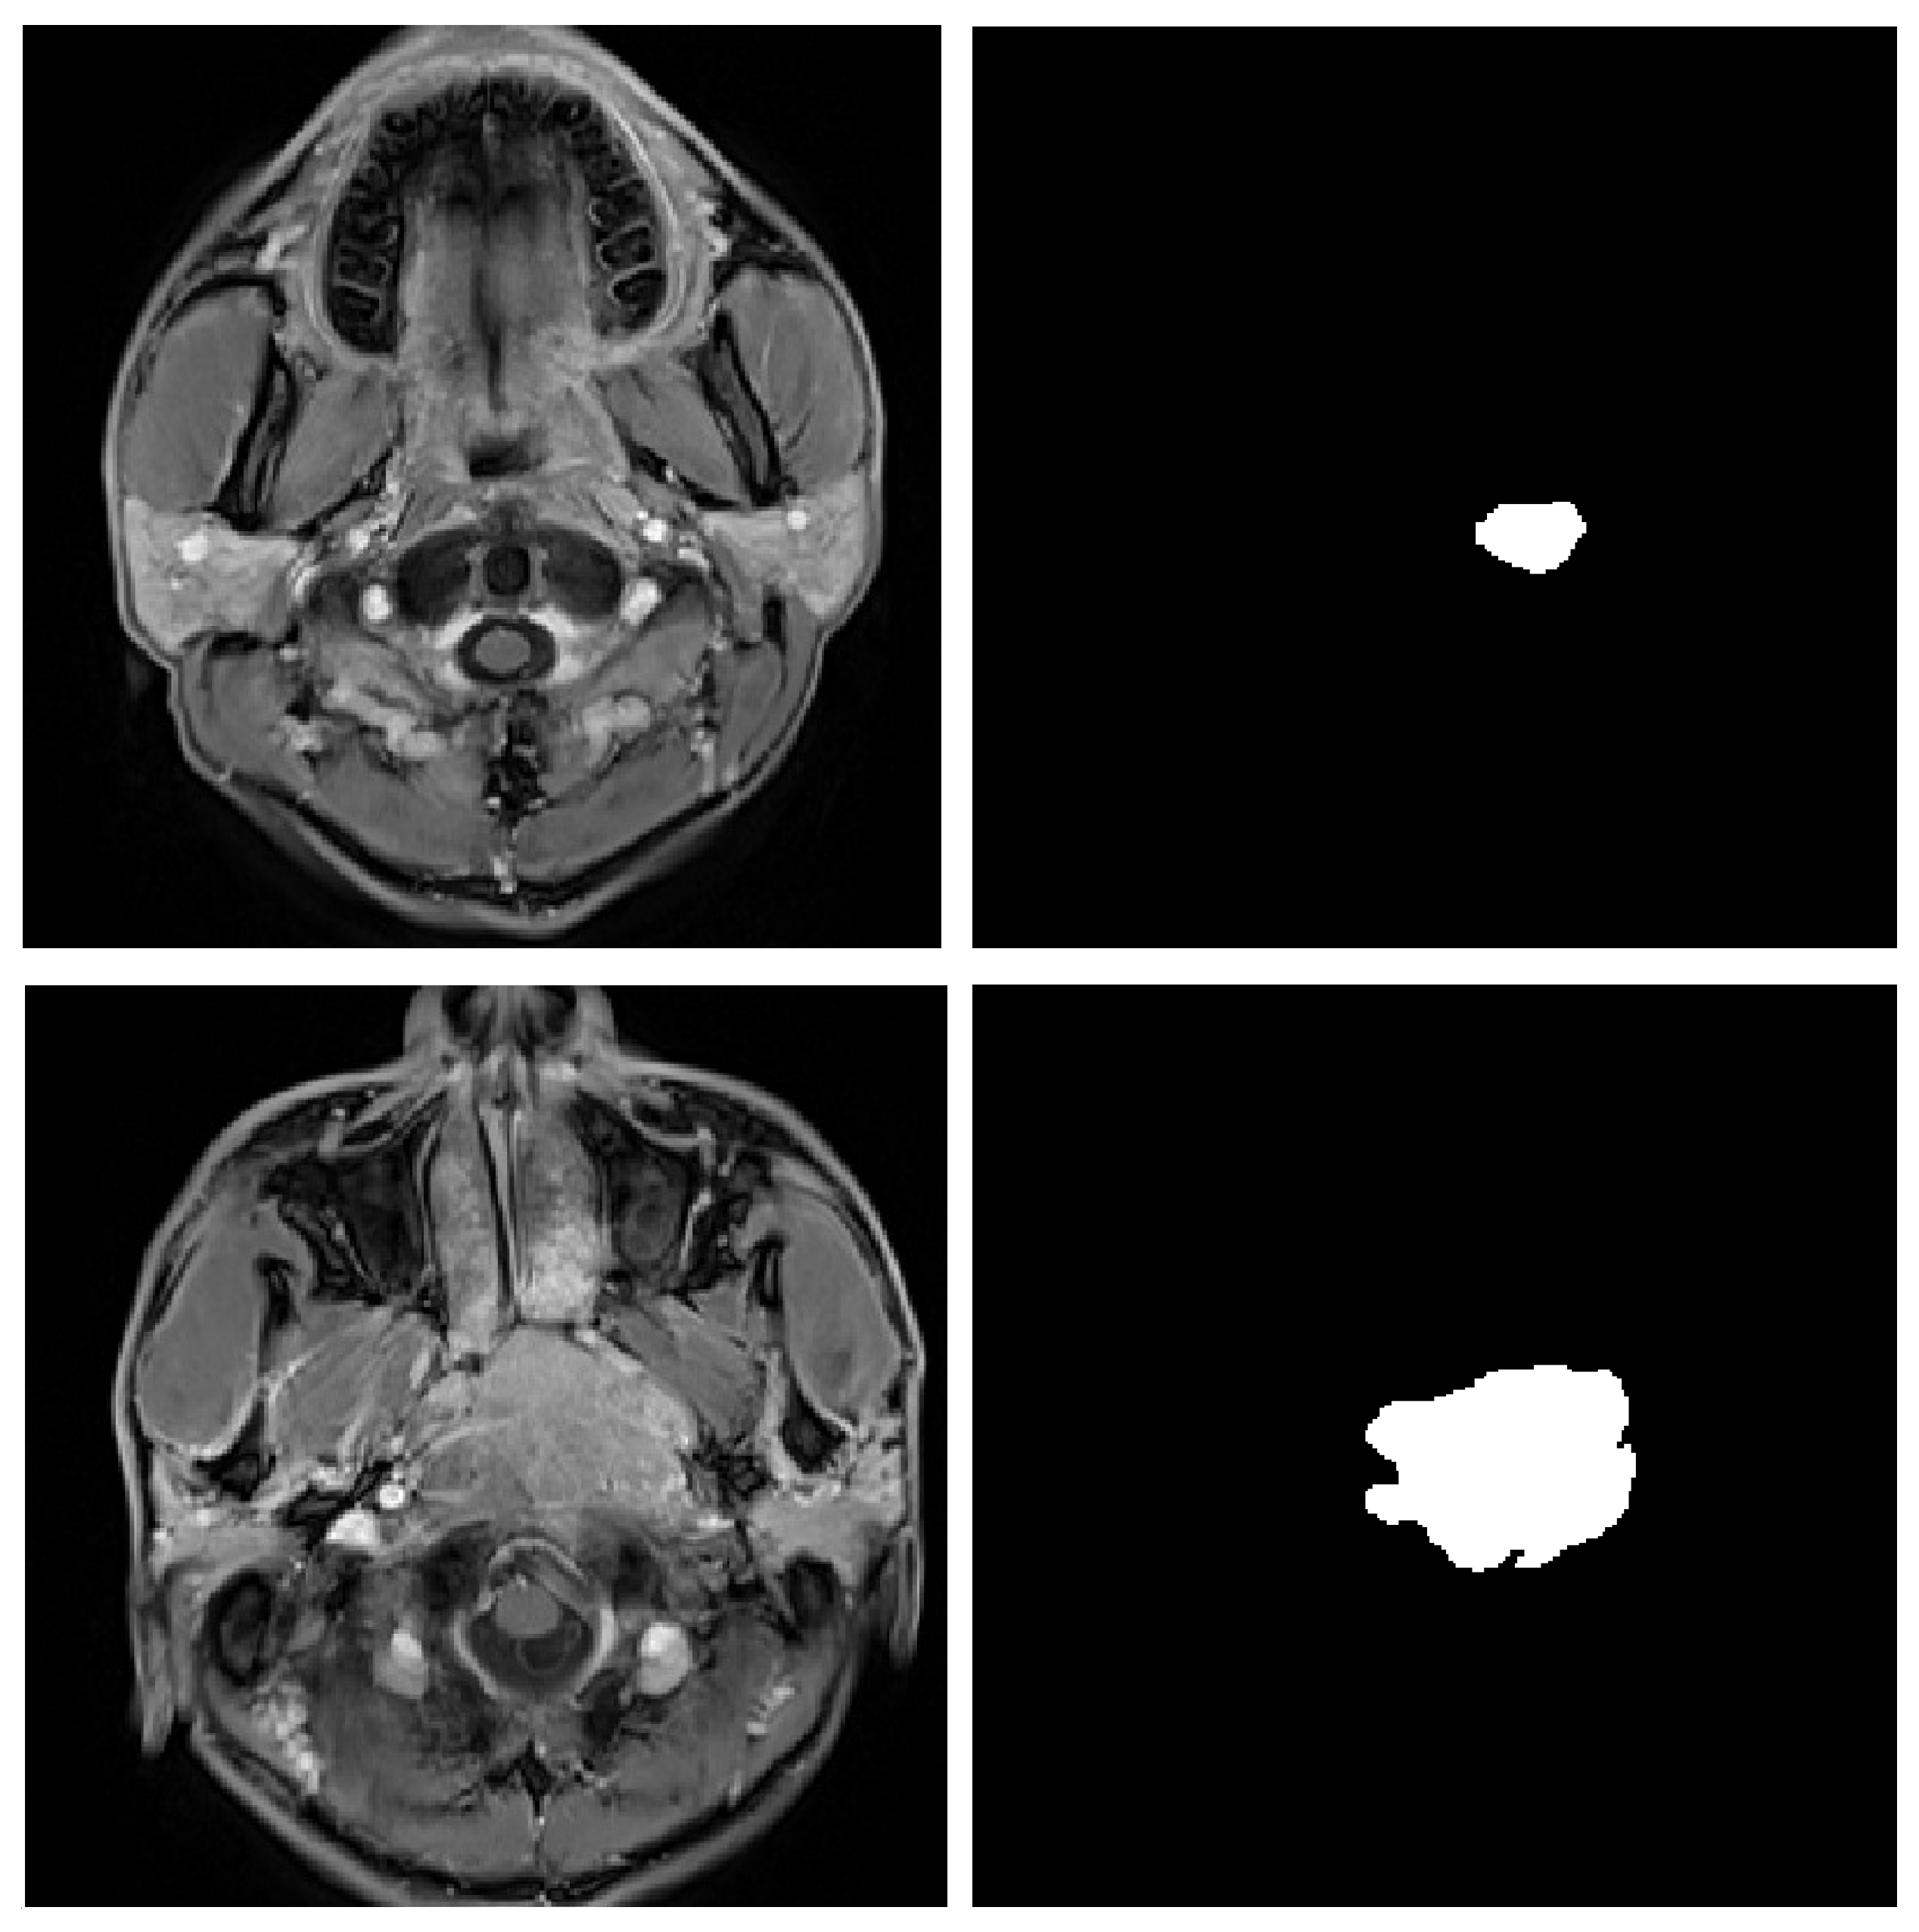

Figure 1.

A sample of the significant variation of the scales of tumors. Most current methods are not able to perform consistently precisely on such slices with noticeable different scales.